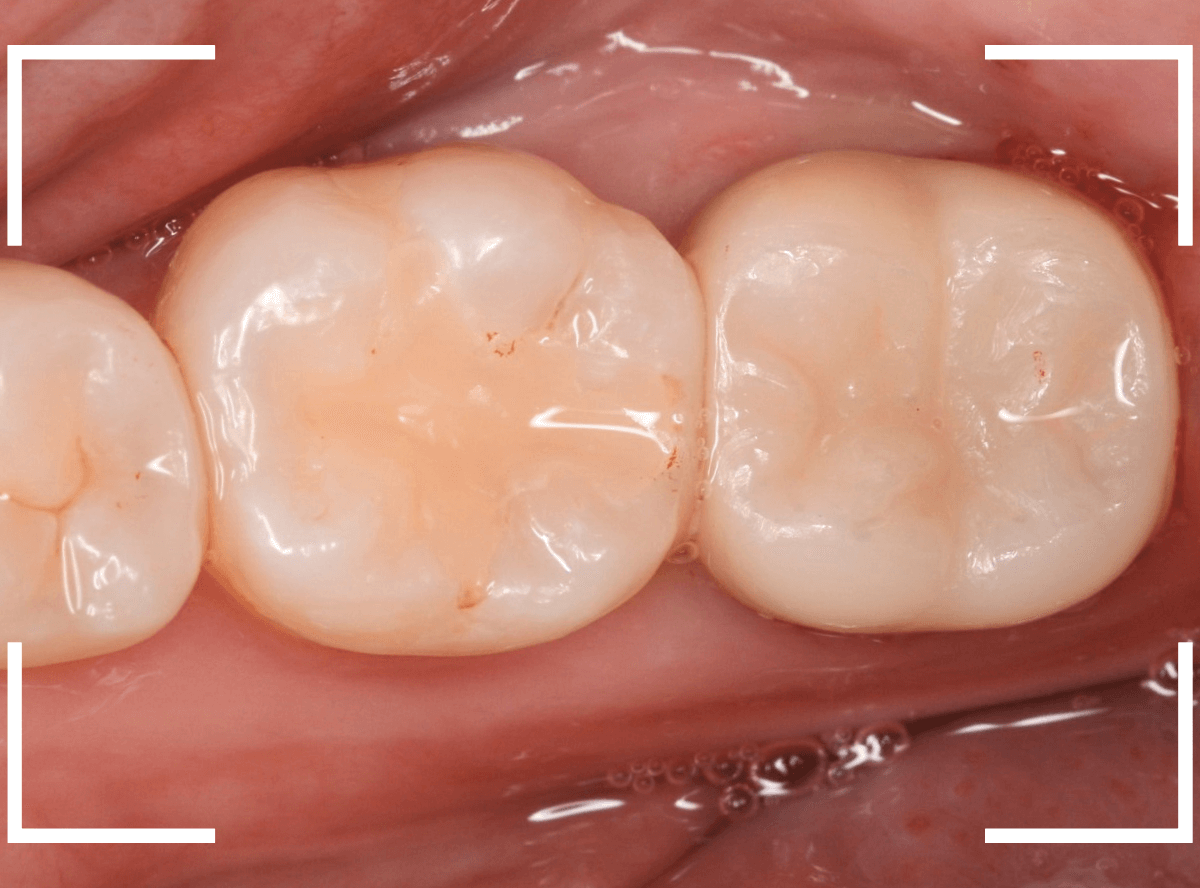

set後の写真です。

患者さんにも満足していただける仕上がりになりました。

治療前後の比較写真になります。